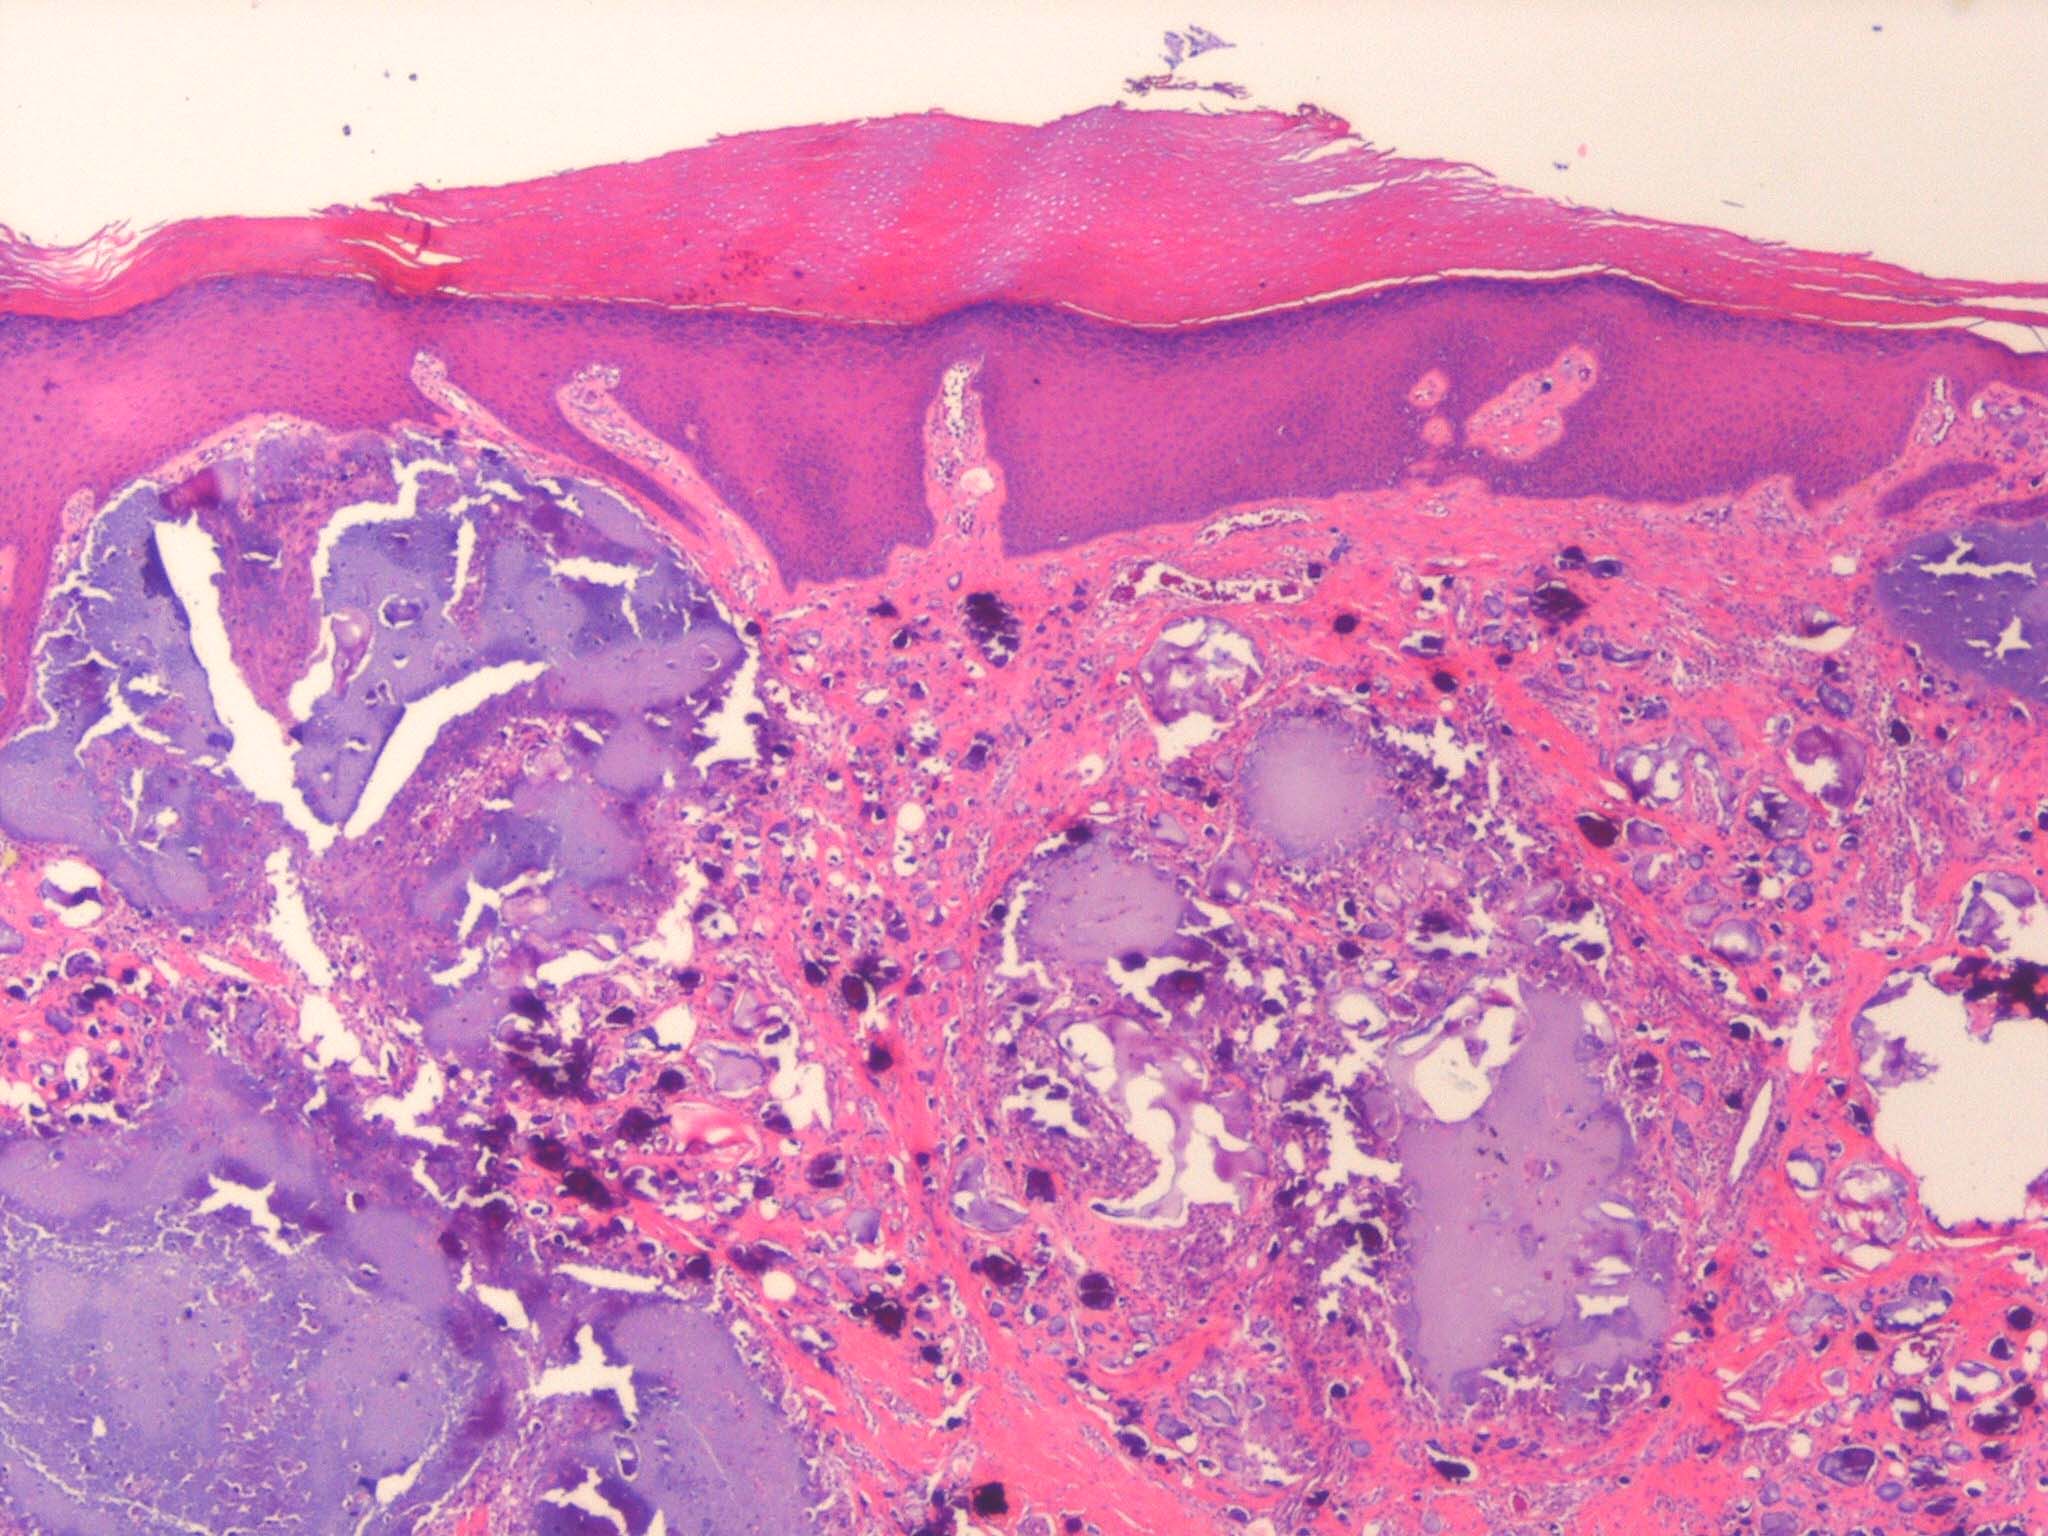

. Calcium deposits are recognized easily in histologic sections, because they stain deep blue with H&E. They stain black with the von Kossa stain for calcium phosphate. As a rule, the calcium occurs as massive deposits when located in the subcutaneous fat and usually as granules and small deposits when located in the dermis (Fig. 17-12). Large deposits of calcium often evoke a foreign body reaction; thus, giant cells, an inflammatory infiltrate, and fibrosis may be present around them .

As in metastatic calcinosis cutis, the calcium in dystrophic calcinosis cutis usually is present as granules or small deposits in the dermis and as massive deposits in the subcutaneous tissue . A foreign­body giant cell reaction is often found around large deposits of calcium . The calcium deposits usually are located in areas in which the collagen or fatty tissue appears degenerated as a result of the disease preceding the calcinosis.